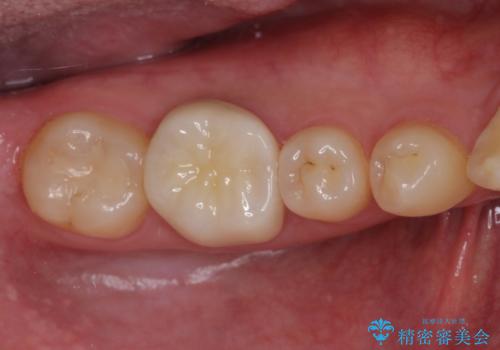

長年気にしていた銀歯を自然な色合いのセラミッククラウンに仕上げることができ、患者様には大変満足していただきました。